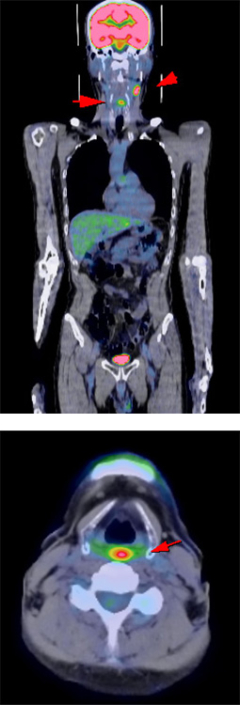

⑥CTやMRIなどと組み合わせるとより詳しくがんがわかります

CTやMRI検査は、体の中の組織や細胞の「かたち」を画像でとらえ、周囲臓器との関係をみることによってその異常を見つけます。これに対しPET検査は、細胞の「活動状態」を画像でとらえる検査法です。

PET検査を組み合わせることで、違った種類の情報が加わり、CTやMRIなどの検査だけでは見つかりにくかったがんが、発見しやすくなります。

またPETはCTやMRIに比較して空間分解能が低く異常が発見されても病気がどこにあるかはっきりわからない場合があります。そこでCTやMRIなどと合成(フュージョン)すると、病変部位の解剖学的な「形や大きさ」を正確に把握することができます。

▲早期右乳癌